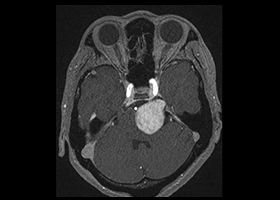

② 神経鞘腫

神経鞘腫は神経の外側を覆っている膜(鞘:さや)から発生する腫瘍で、多くは軟部組織の末梢神経から発生します。中枢神経系では、大部分が第8脳神経(聴神経)より発生し難聴や小脳失調、水頭症などの原因となります。まれに第5脳神経(三叉神経)やその他の脳神経にも発生します。良性腫瘍ですから、完全に切除できれば再発はありません。しかし、頭蓋内神経鞘腫は小さい病変であれば摘出が可能ですが、大きな病変となり、脳神経や血管、脳を巻き込むようになると手術で完全に摘出することは困難となります。外科的切除のほかに放射線治療も行われています。予後は良好ですが、神経の機能障害が残ることがあります。

症例1)52歳女性 左聴神経鞘腫、外科治療のみ

[画像所見]

-

術前MRI:右内耳道内に脳腫瘍を認めます。